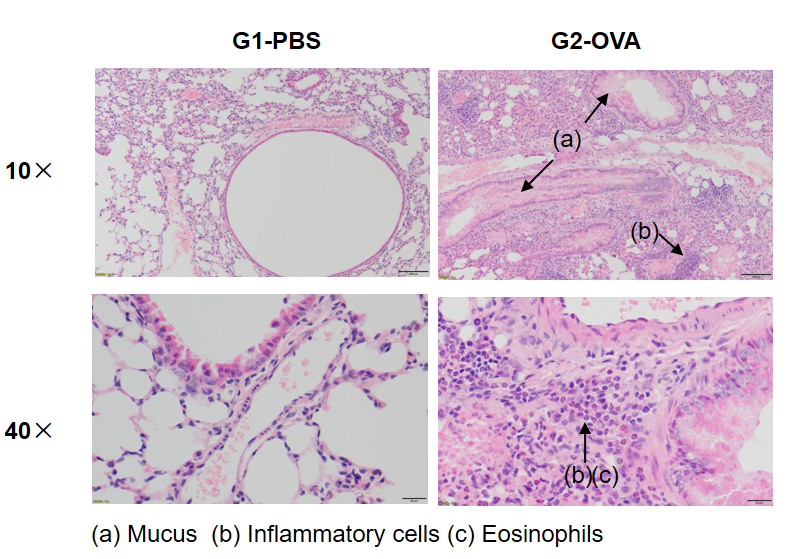

Airway Histology in Asthmatic Mouse Model

OVA successfully induces asthma-related pathology in wild-type C57BL/6 mice. H&E staining of lung tissue shows asthma-related pathology in OVA-treated (G2) mice, including vascular and peribronchial inflammation (b) and mucus (a) accumulation in some bronchi, compared to the untreated (G1) group.